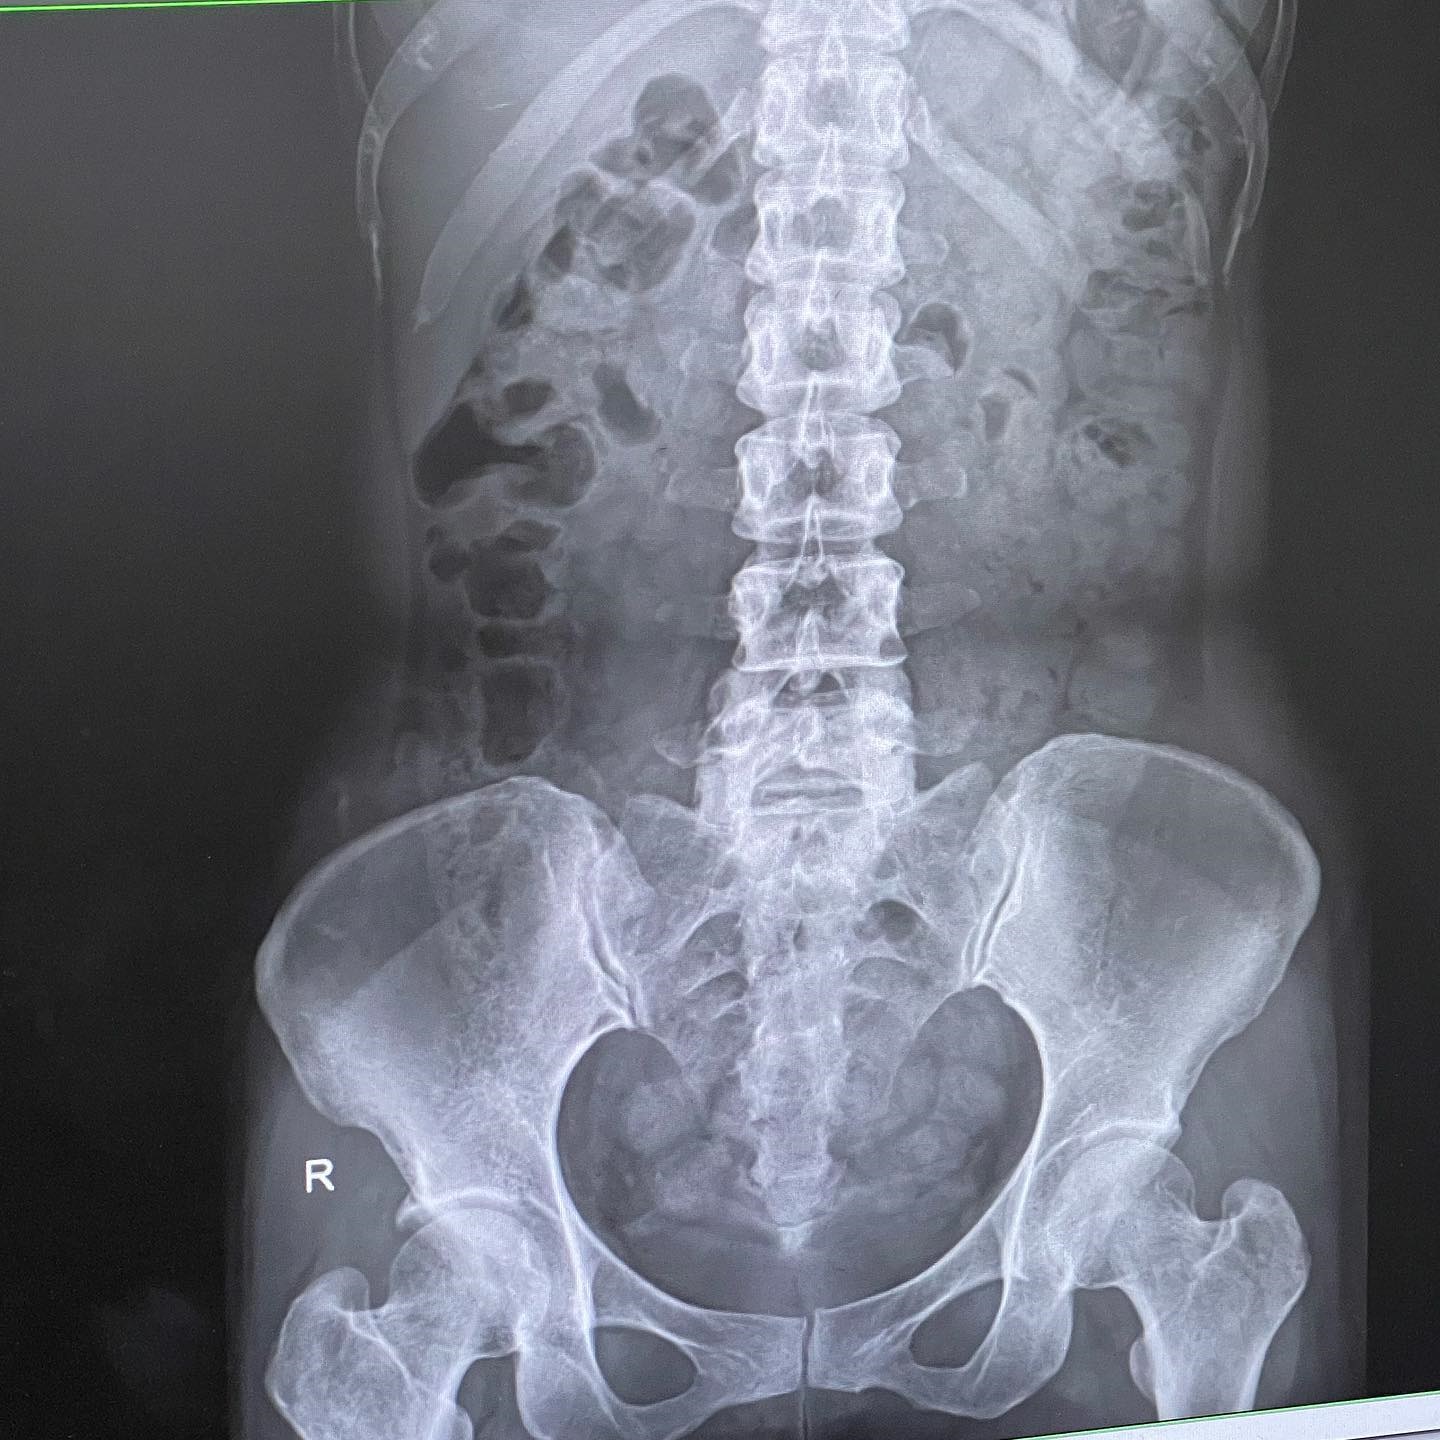

กลายเป็นข่าวฮือฮาเลยทีเดียว หลังจากนักร้องสาว ตุ๊กตา จมาพร หรือ ตุ๊กตา The Voice ออกมาแชร์ประสบการณ์ป่วยแปลก ด้วยโรคขี้เต็มท้อง โดยได้เล่าอาการของตัวเอง รีวิวหลังพบแพทย์ พร้อมทั้งให้คำแนะนำสำหรับคนที่มีอาการคล้าย ๆ กัน จนหลายคนสงสัยว่าตัวเองจะป่วยแบบนี้ด้วยหรือเปล่า